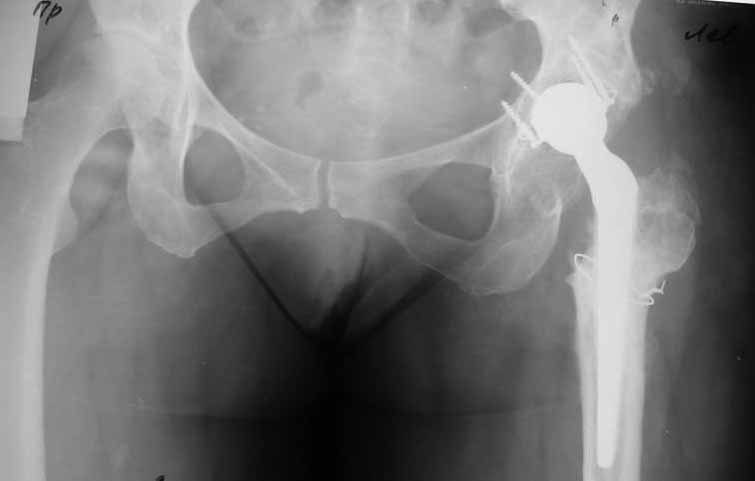

Пациентка 45 лет. Бесцементное эндопротезирование левого тазобедренного сустава 6 лет назад (впадина RM, Mathys, металл-металл, ножка Зульцеровская). За 10 лет до протезирования – коррегирующая остеотомия бедренной кости, которая не срослась в течение года до удаления пластины, а затем срослась в течение 3 месяцев иммобилизации в кокситной повязке. После протезирования получилось наблюдать пациентку почти постоянно, поскольку через 2 года синтезировал ей лодыжки на оперированной стороне, затем, через несколько месяцев удалил фиксаторы, а в 2009г. резецировал мениск на противоположной стороне. Боли все эти годы не беспокоили. Пациентка чуть выше среднего роста, вес тела нормальный. Физические нагрузки переносила хорошо. Работает на 7 этаже без лифта. Год назад экстирпация матки по поводу лейомиомы больших размеров. Несколько месяцев назад появились боли в области левого тазобедренного сустава. При рентгеновском и КТ исследованиях (июль с.г.) – нестабильность тазового компонента. От предложенной замены протеза пациентка на тот момент, слава богу, отказалась. Через какое то время боли в области левого тазобедренного сустава практически полностью прошли, а около 2 месяцев назад появилось ощущение патологической подвижности таза и боли в паху справа, которые через некоторое время уменьшились, а потом снова усилились после значительных физических нагрузок (много ходила по песку на пляже, носила тяжести). Ежедневно принимала диклофенак. На рентгенограммах – переломы правой лонной кости. Сейчас госпитализирована из-за болей в паху справа. Боли слева не беспокоят. На фоне снижения нагрузок в стационаре боли значимо уменьшились. Способна ходить без средств дополнительной опоры.

-правильно ли я расцениваю переломы как стрессовые на фоне неполноценного таза (pelvic insufficiency stress fractures)?

-Можно ли так же расценить ситуацию на стороне протеза и, соответственно, не торопиться с ревизией, рассчитывая на вторичную стабилизацию? Уж больно не хочется менять ножку.

На представленных снимках тазобедренный сустав до и сразу после операции, затем 2 снимка 2009г., когда ничего не беспокоило, затем КТ 2-х месячной давности и вчерашние рентгенограммы обоих тазобедренных суставов.